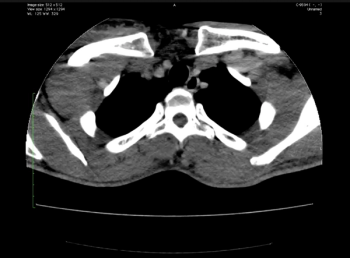

What is this seen post bypass surgery along the aorta?